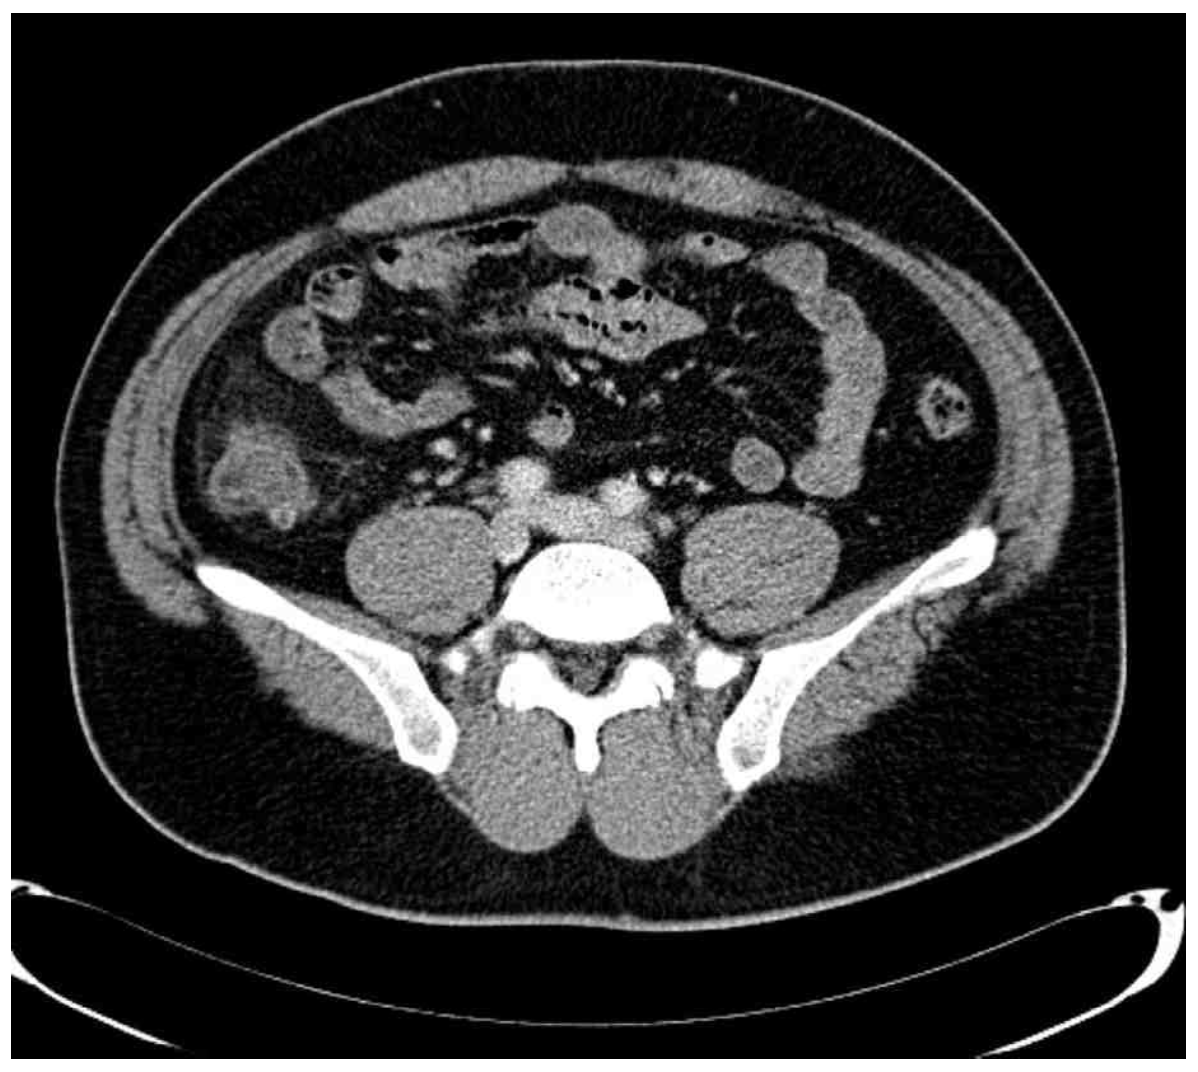

57세 남자가 1일 전에 혈변을 봤다며 병원에 왔다. 혈압 110/65 mmHg, 맥박 120회/분, 호흡 20회/분, 체온 37.2°C이다. 오른쪽 아랫배에 압통이 있고 반동압통은 없다. 혈액검사 결과는 다음과 같다. 복부 X선사진과 복부 컴퓨터 단층촬영 사진이다. 진단은?

CT: localized bowel wall thickening and inflammation findings(hazziness) in RLQ

CT상 diverticulum 및 inflammation 소견이 보이며, 혈액검사에서 염증 소견이 확인되므로 게실염으로 진단한다.

• AXR상에선 특이소견이 관찰되지 않았지만, 복부 CT상 우하복부 위치에서 diverticulum 및 주위에 지저분한 음영이 관찰된다. 환자의 임상증상 및 혈액검사 결과와 종합하여 생각할 때, 염증성 병변으로 인한 소견으로 생각된다.

• 우하복부 위치에서 diverticulum이 확인되고 주변에 염증성 소견 또한 관찰되므로 곁주머니염(diverticulitis)으로 진단한다.